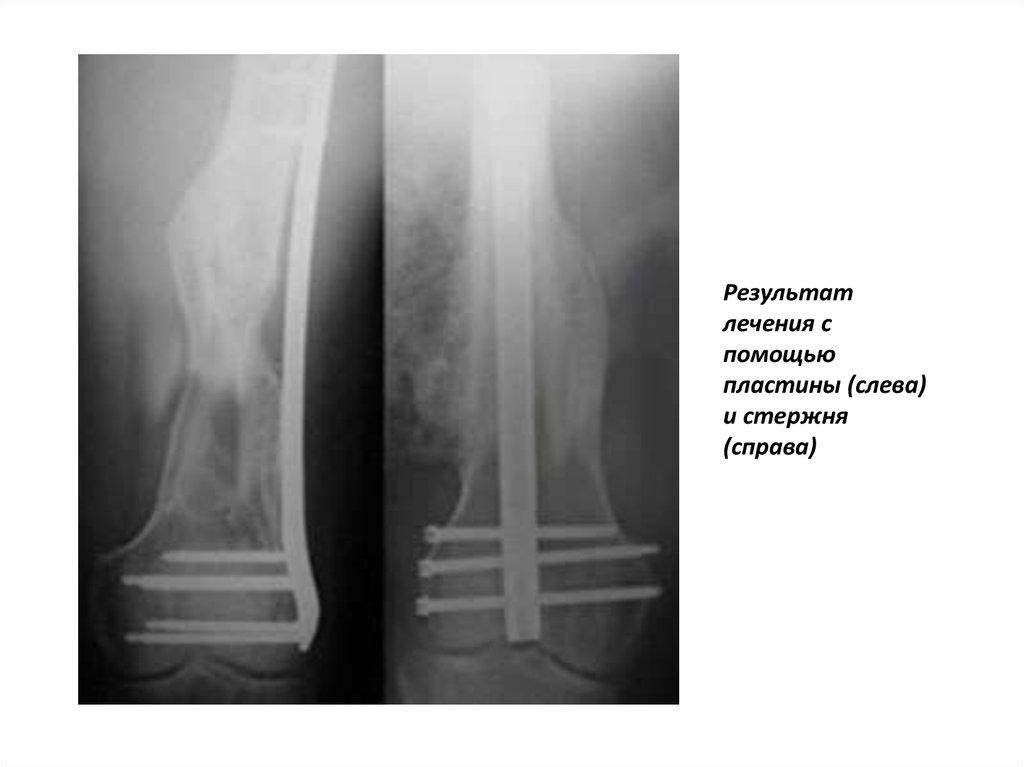

Результат

лечения с

помощью

пластины (слева)

и стержня

(справа)